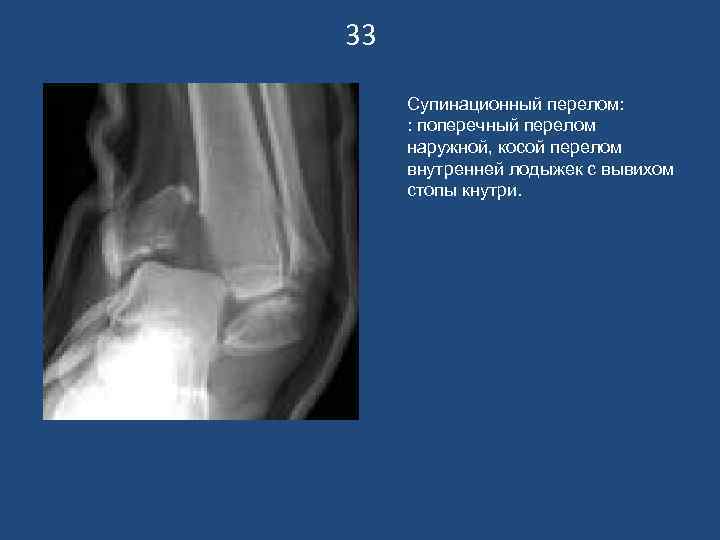

33 Супинационный перелом: : поперечный перелом наружной, косой перелом внутренней лодыжек с вывихом стопы кнутри.